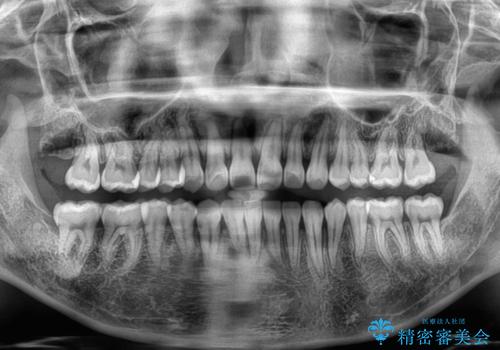

上顎歯列が下顎の歯列に対して狭小であり、一部下顎の奥歯が上顎よりも外側に位置している状態でした。

上顎の急速拡大装置を使用して上顎骨を側方に拡大することで上顎歯列を拡大し、下顎歯列も拡大できるようにすることで、歯列を整えることとしました。

歯列矯正では基本的に骨格を改善することはできませんが、急速拡大装置(MARPE)を使用することで上顎骨を側方に拡大させることができ、咬合状態を大きく改善することができます。